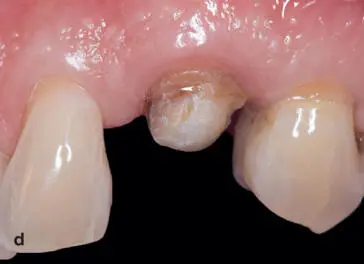

Fig 1-22 (a and b) The patient presented with a subgingival fracture of the maxillary left canine with caries. (c) After anesthesia, bone sounding confirmed that gingival resection would provide an adequate ferrule without infringing on the biologic width. A treatment plan was discussed with the patient that included crown lengthening of the canine to establish a ferrule effect of 1 to 2 mm, endodontic therapy, and placement of a fiber-reinforced post and core as well as an all-ceramic restoration. (d) Before restorative treatment was initiated, a gingivectomy was performed to gain sound coronal tooth structure. (e) After endodontic therapy was performed, a fiber-reinforced post and core was completed. (f) The provisional restoration (G-aenial Universal Flo) was fabricated from a clear matrix of the diagnostic wax-up using a polyvinyl siloxane impression material (Exaclear, GC America). The provisional restoration was fabricated intraorally using the inverse injection-layering technique, using A1- and B1-shaded flowable resin composite (G-aenial Universal Flo). The provisional restoration guided the tissue shaping and required 3 months to develop the emergence profile. (g) The completed zirconia ceramic crown on the maxillary left canine. (h) Note the healthy biologic framework and the integration of color with the adjacent dentition.